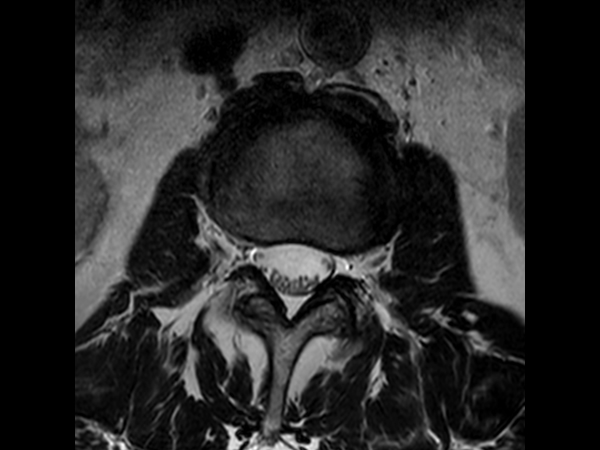

Comprehensive Lumbar Spine imaging at 3.0T